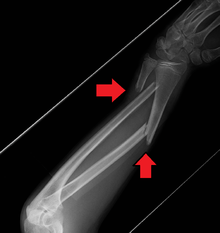

Fracture

Midshaft fracture of the radius and ulna

A fracture of the forearm can be classified as to whether it involves only the ulna (ulnar fracture), only the radius (radius fracture) or both (radioulnar fracture)